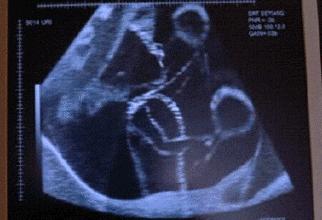

怀孕期间胎动频繁是正常的情况吗?很多妈妈都很担心自己的必备胎动频繁会不会是多动症的表现,其实胎动频繁是属正常情况,不过什么时候的胎动最频繁呢?来看看这些妈咪经验吧。

胎动反映出宝宝的健康状态,所以妈妈们要多加留心宝宝的动作,出现这些异常的胎动情况,妈妈就要注意咯: